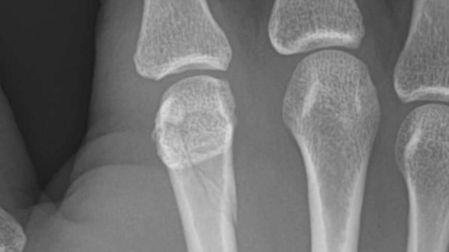

Horas después del combate, Mario compartió una radiografía de su mano lesionada junto a un mensaje que rápidamente se volvió viral:

Nudillo roto, Canelo voy por ti”.